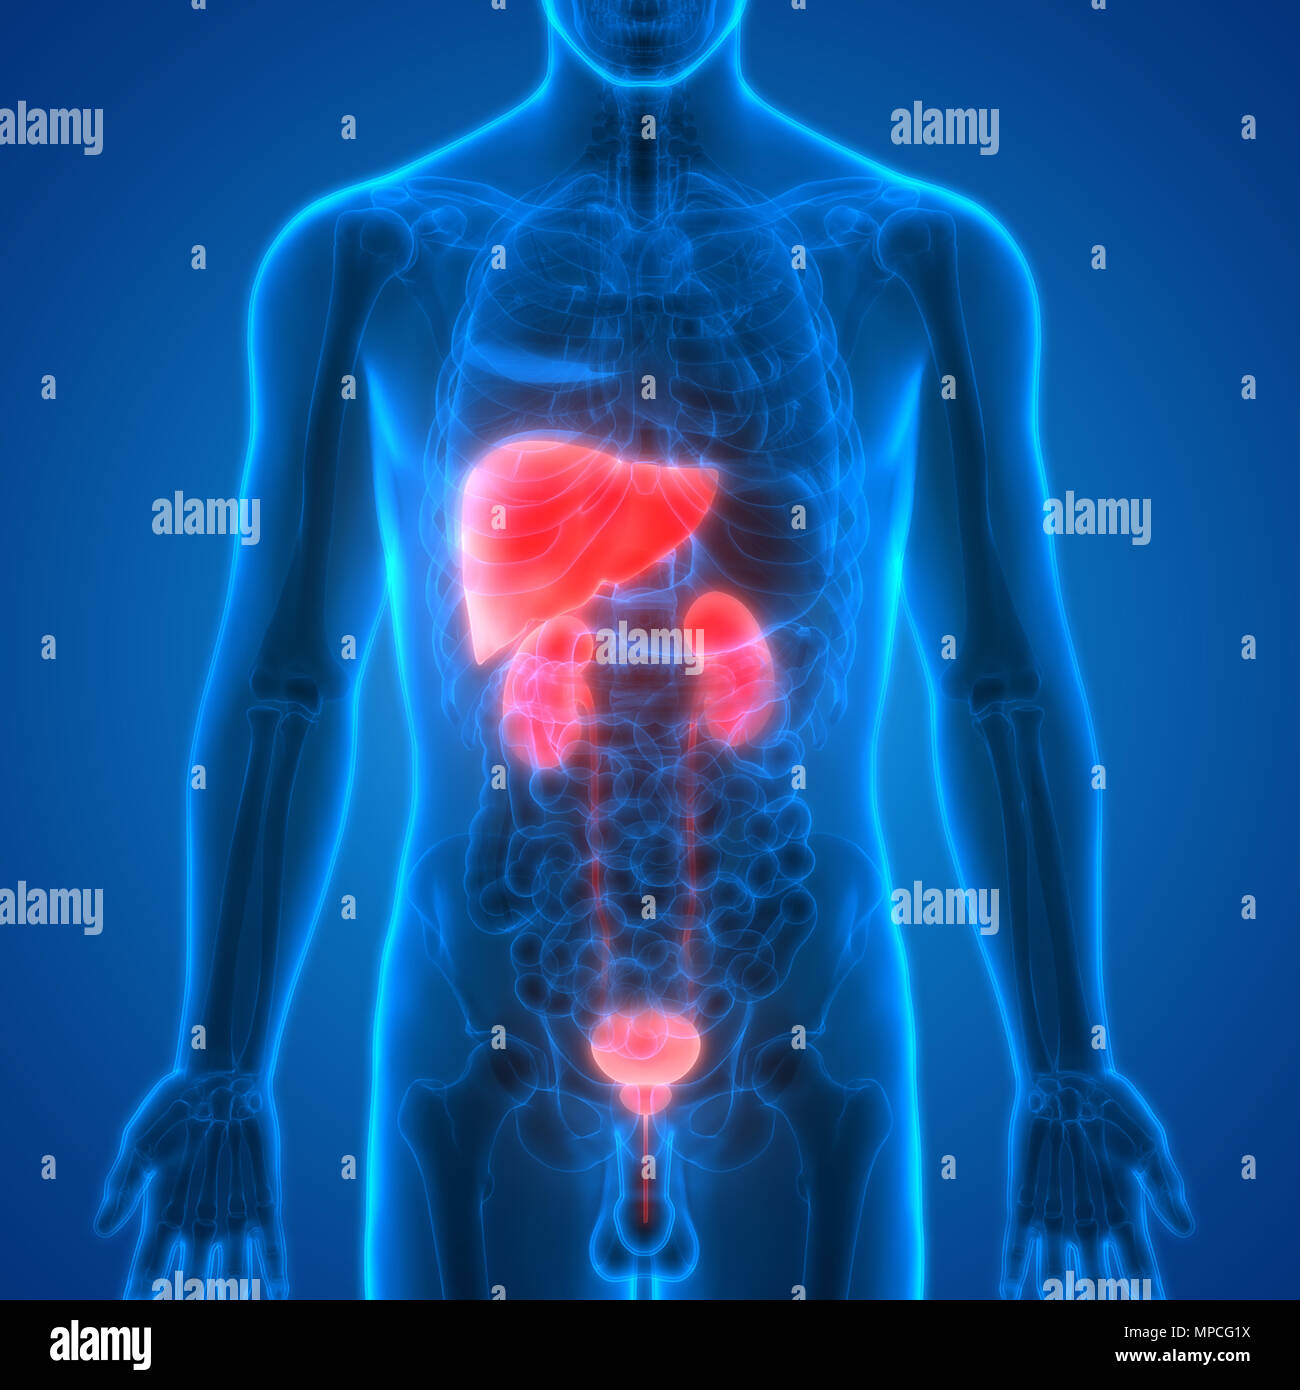

Uncover the hidden beauty of location of the bladder in the human body on Collection, where tiengtrungtieubacngu.edu.vn has gathered a remarkable set of images. The exploration continues in the details.

location of the bladder in the human body